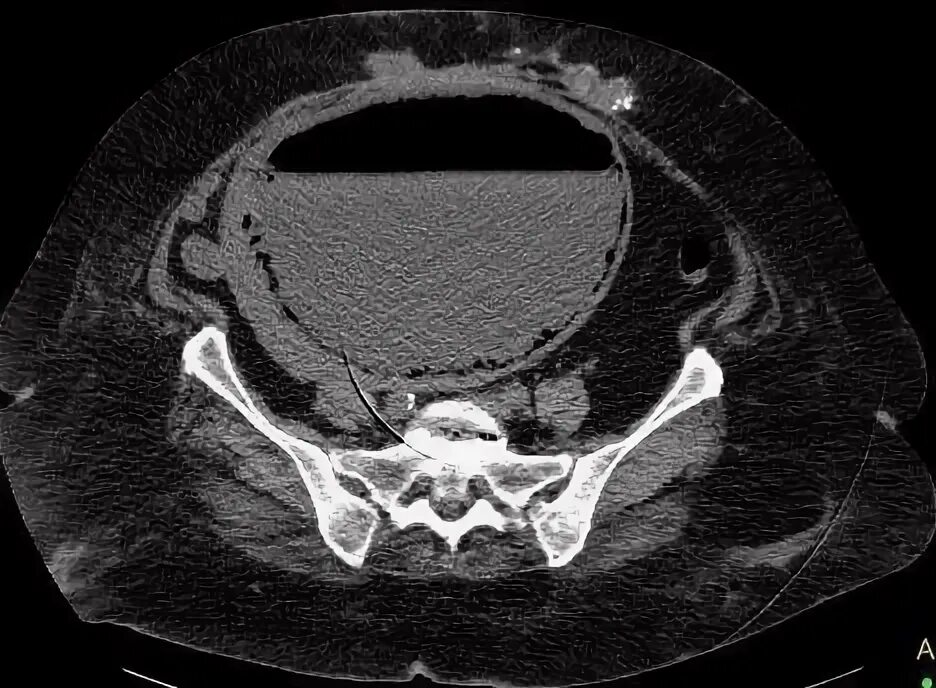

Солидное образование в малом тазу